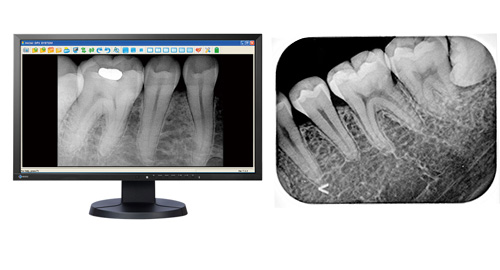

レントゲンにはお口全体を撮影するパノラマレントゲンと2~3本の歯を撮影するデンタルレントゲンがあります。

それに対して、小さいサイズのデンタルレントゲンは細かな虫歯や根の先の状態などパノラマレントゲンよりも詳しい情報を得ることができます。